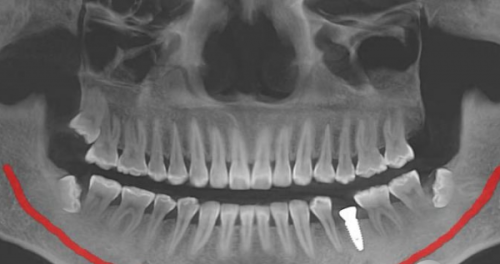

医生团队是医院的核心竞争力之一。以牙齿矫正医生为例,他们不仅具备扎实的理论知识,还在实践中积累了大量的成功实例。在技术优势上,维乐口腔不断引进精良的口腔医疗设备,如口腔CT、数字化正畸系统等,提高了诊断和治疗的正确性和效率。从口碑方面来看,在各大医疗评价平台上,都能看到患者对北京维乐口腔的高度评价,称赞其技术好、服务优。